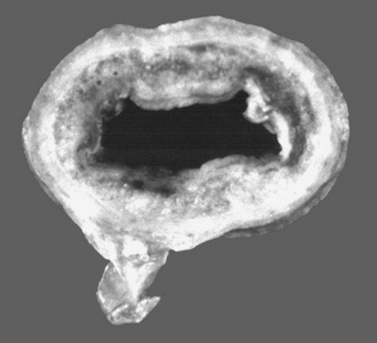

The heat-stable endotoxic activity of Vibrio cholerae identified by Pfeiffer more than 100 years ago resides in LPS, the principal component of the outer leaflet of the outer membrane of all gram-negative bacteria (Fig. 32-40).274 Each LPS molecule has three structural domains: a polar polysaccharide O-region, which projects into the aqueous extracellular environment; a hydrophobic lipid A region, which is largely buried in the bacterial outer membrane; and a core acidic oligosaccharide region connecting the two. The O-region is highly variable, consisting of repeating units each of one to eight glycosyl residues, and contains antigens specific for each bacterial strain; the core glycolipid region is relatively constant among bacteria and mediates most of the toxic effects of endotoxin. On bacterial death or during bacterial proliferation, large (>106-dalton molecular mass) aggregates of LPS and membrane protein are released. It is these protein-lipid micelles that constitute native endotoxin and are to be found circulating in naturally acquired cases of endotoxemia. In recognition of the fact that most endotoxic activity resides in the LPS component, the terms endotoxin (the activity) and lipopolysaccharide (the molecule) are used interchangeably except when a specific or purified LPS is being referenced.275

Fig. 32-40 Cross-section of the double lipid bilayer that forms the cell membrane of gram-negative bacteria. As is shown in this figure, lipopolysaccharide (LPS) is the principal component of the outer leaflet of the outer membrane. The insert shows a single LPS molecule with an O-polysaccharide chain, a two-part core oligosaccharide, and a hydrophobic lipid A phospholipid. R-mutant bacteria lack the O-chain ± varying amounts of the core oligosaccharide.